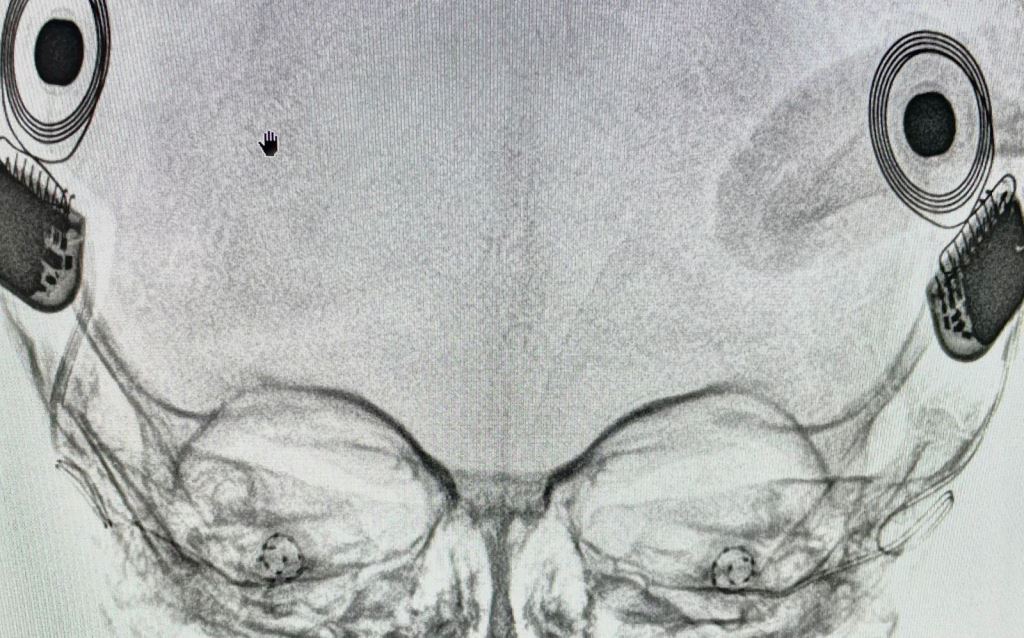

According to reports, over 27,000 children are born with congenital hearing loss in India each year. In Baby Shraddha’s case,  she was screened for hearing loss when the parents noticed that she did not respond to sounds and had not spoken yet. She was evaluated in West Bengal when she was 9 months old. Further radiological evaluation was done at Aster RV Hospital and she was deemed fit to undergo bilateral cochlear implant surgery.

Dr. Rohit Udaya Prasad, Lead Consultant – ENT and Cochlear Implant Surgery, Aster RV Hospital said, “Hearing loss in a baby can be treated with the help of hearing aids or cochlear implants depending on the severity of the hearing loss. In Shraddha’s case, we conducted a simultaneous bilateral cochlear implant to help give her a full range of hearing. The operating time was significantly reduced as we used a minimally invasive VERIA technique which would also allow us to discharge her the next day itself so she could go home and recover. With the help of this technology, baby Shraddha should be able to have hearing and speech development.”